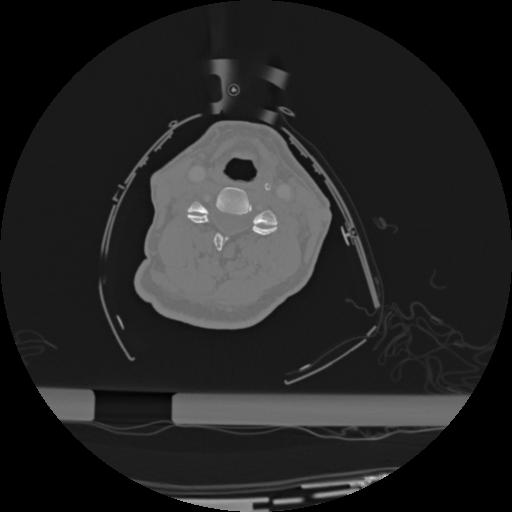

22 ANGIO,CE,Vol,0.5,ANGIO,,